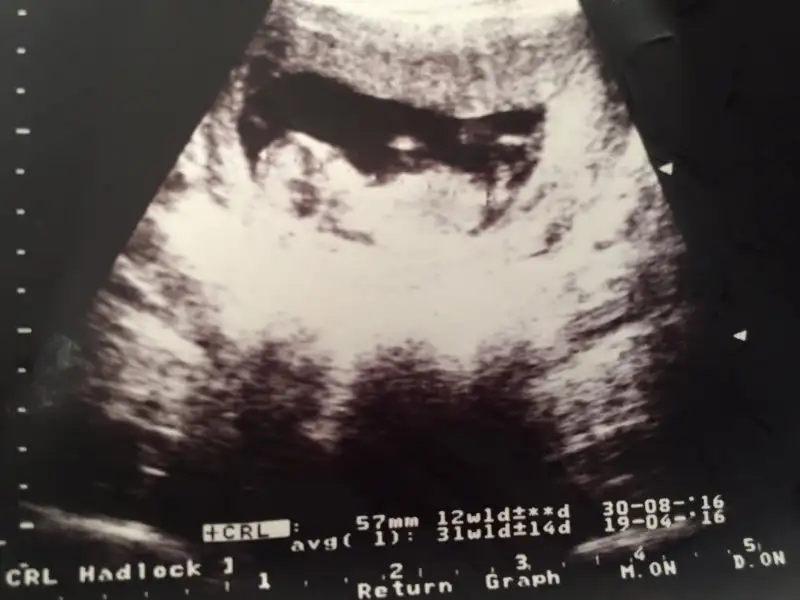

İşt bu da benim

Eklentiler

• image.webp

image.webp

7,4 KB · Görüntüleme: 120